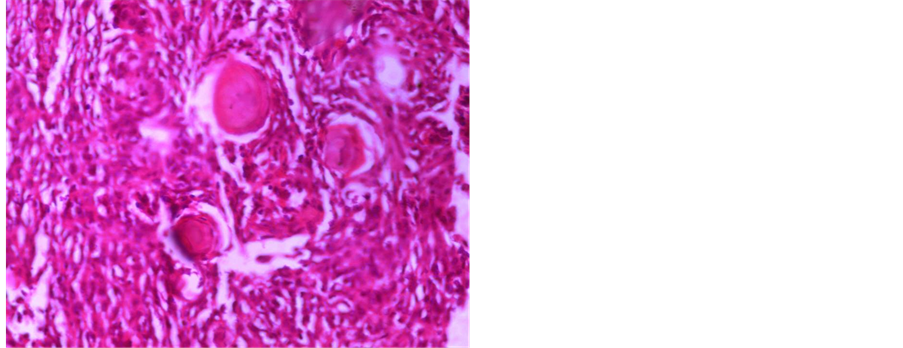

A 61-year-old female patient was with history of spinal trauma in 26 year ago. Patient fall down from height and had a traumatic L1 fracture. Patient was managed conservatively at that time as she refused surgical intervention and had no neurological deficit. Patient experienced frequent attacks of low back pain and rarely sciatic pain that was treated with analgesia. 6 months ago, the patient had a progressive heaviness in both lower limbs with urinary incontinence and visited the outpatient clinic. On examination, the patient was paraparetic with motor power grade II or III below L1. Patient had hypotheisa below L1 with diminished knee and ankle reflexes. MRI lumbar and dorsal spine showed the post-traumatic L1 fracture with a new large intra-dural mass most probably meningioma or schwnoma as shown in Figure 1. Patient operated with posterior lumbar approach including posterior L1 and D12 laminectomy. Total standard microscopic excision of the intra-dural soft tissue mass with moderate vascularity was performed successfully. A posterior D11, D12 and L2 trans-pedicular screw fusion was performed at the end of the procedure. Histopathological examination revealed multiple nodules of proliferated meningothelial cells separated by delicate fibrous tissue, with thick walled blood vessels and calcified psammoma bodies together with oval to rounded cells with oval nuclei, occasional nuclear clearing and infrequent mitosis arranges in whorly pattern with rounded calcified psamma bodies. A meningeothelial and psamomatous meningioma was reported as shown in Figure 2. The patient has smooth postoperative course with improvement of her neurological deficit with physiotherapy. 4 months after surgery, the patient was able to ambulate without assistance. On her last follow up after one year of surgery; the patient has no neurological deficit and can ambulate without assistance

Figure 2. (a) Photomicrograph showing multiple nodules of proliferated meningothelial cells separated by delicate fi- brous tissue, with thick walled blood vessels and calcified psammoma bodies, H & E × 40 (b) and (c) Photomicr- graph of meningioma showing oval to rounded cells with oval nuclei, occasional nuclear clearing and infrequent mi- tosis arranges in whorly pattern with rounded calcified psammoma bodies, H & E × 400.